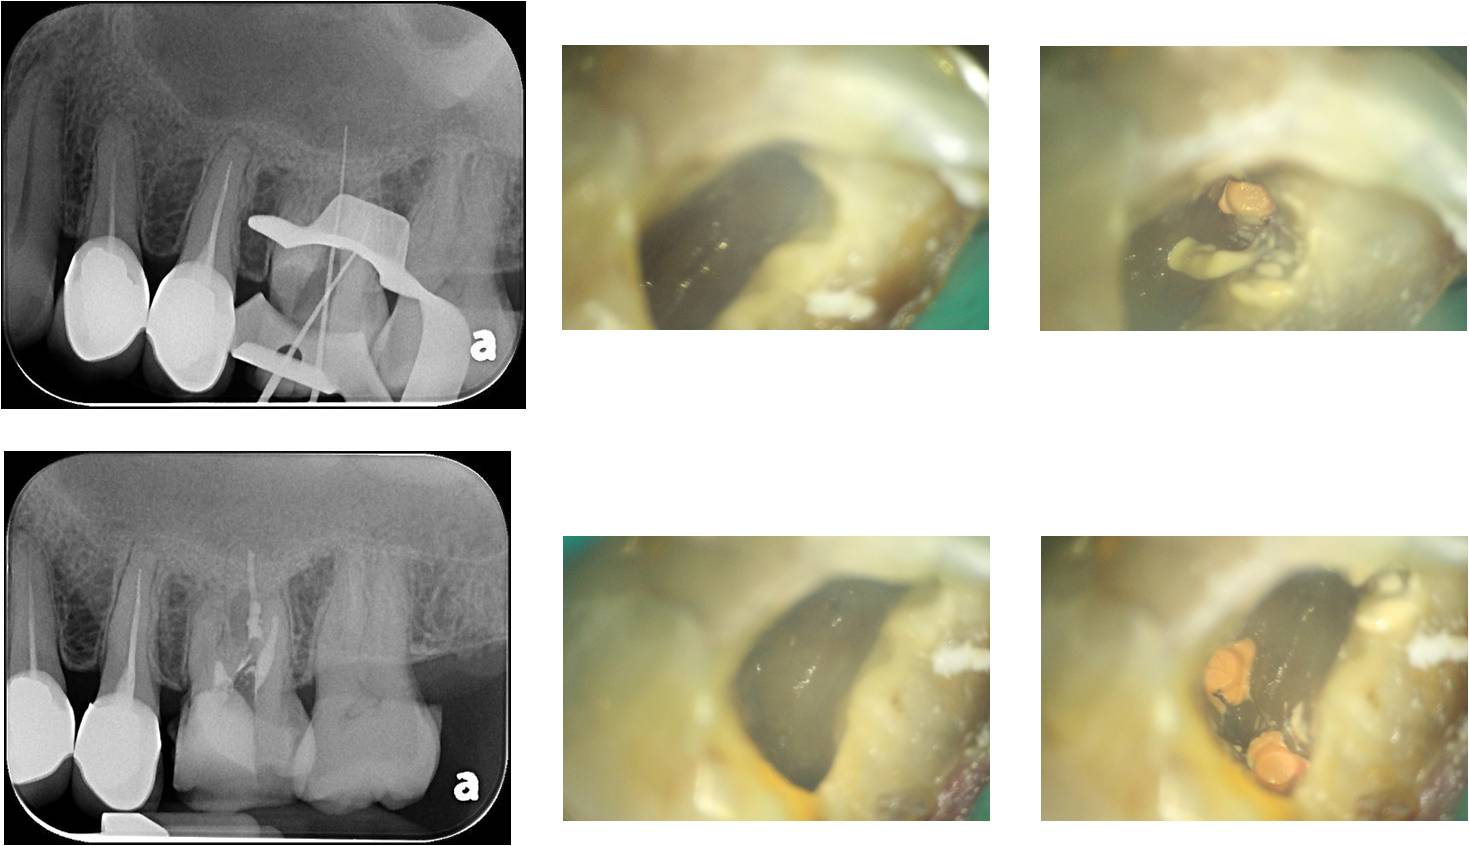

牙冠增長手術

牙齒製備